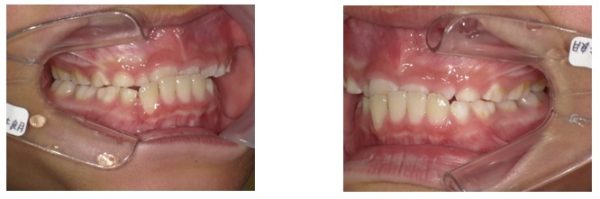

西村歯科医院に、ご相談に来た患者さんです。

生年月日 平成〇〇年12月〇〇日 8歳4か月 男性

(症状、患者さんの主訴について)

①反対咬合

②嚥下障害

③咀嚼障害